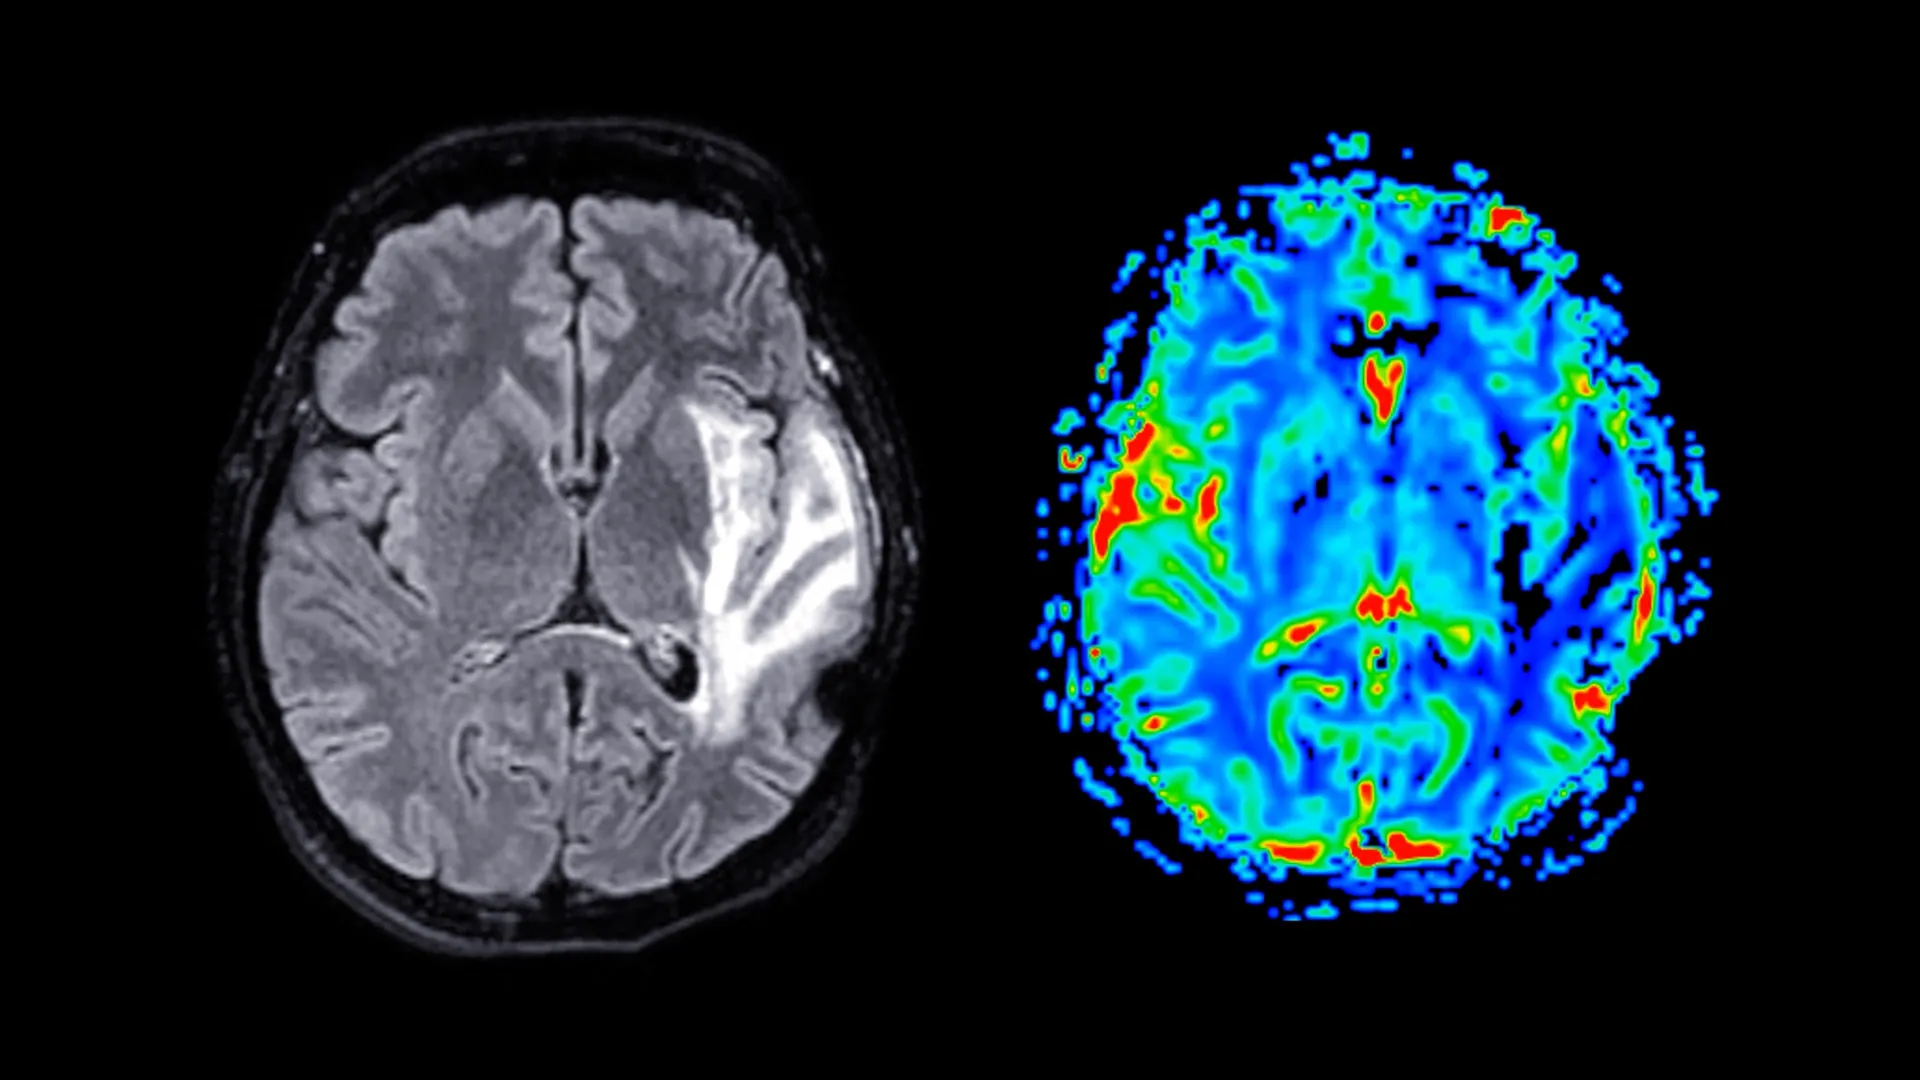

Participants in the study provided a wealth of self-reported information through comprehensive questionnaires. These surveys delved into the specifics of their menopausal symptoms, their mental health status, their sleep patterns, and their general health and well-being. Furthermore, a subset of these women underwent standardized cognitive assessments designed to evaluate key aspects of their memory and reaction times. The study also incorporated advanced neuroimaging techniques, with approximately 11,000 women participating in Magnetic Resonance Imaging (MRI) scans. These scans provided invaluable structural data of the brain, enabling researchers to identify and quantify differences in brain volume and composition.

The most striking findings emerged from the brain imaging data. MRI scans revealed significant reductions in grey matter volume among post-menopausal women, irrespective of their HRT status. Grey matter, a critical component of the central nervous system, is densely packed with neuronal cell bodies. It plays a pivotal role in a vast array of cognitive functions, including information processing, motor control, memory formation, and emotional regulation.

The specific brain regions exhibiting the most pronounced grey matter reduction were particularly noteworthy. These included the hippocampus, a structure fundamental to the formation and consolidation of new memories; the entorhinal cortex, often described as the "gateway" for information flow between the hippocampus and other brain areas; and the anterior cingulate cortex, which is instrumental in managing emotions, facilitating decision-making, and directing attentional focus. The vulnerability of these specific regions is of significant concern given their known involvement in neurodegenerative diseases.